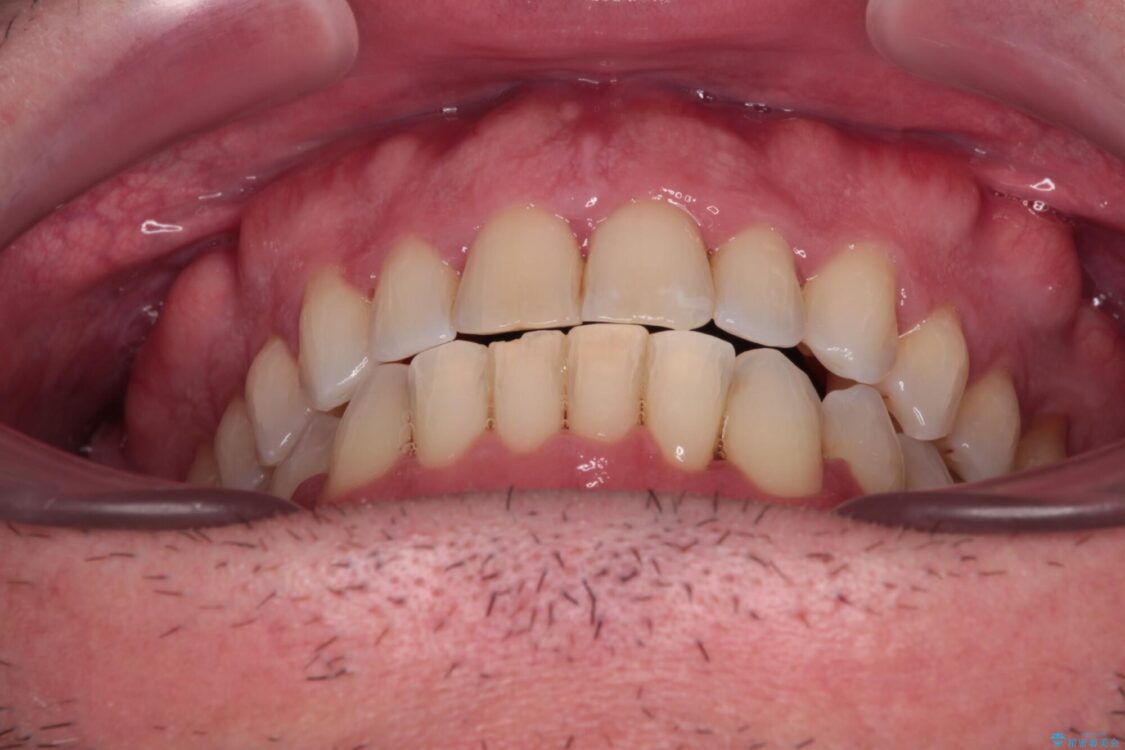

治療後について

舌のトレーニング自体は簡単なものですが、無意識下でも舌が突出しないようにしなければならないため、毎日継続することが最大の難関です。

時間はかかりましたがトレーニングを頑張ってくださり、無事に前歯を接触させることができました。

治療後